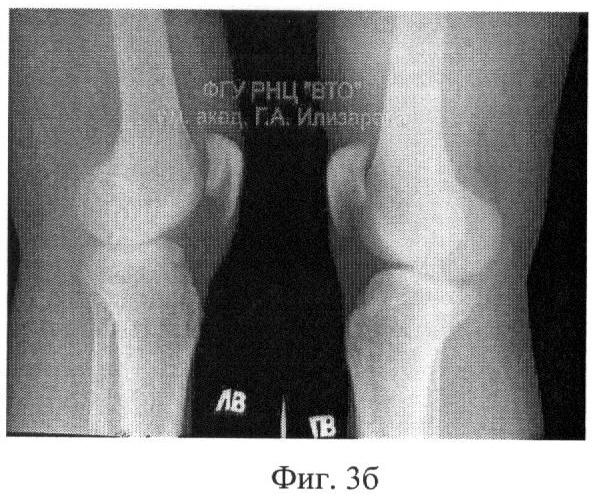

Фиг.3 – рентгенограмма коленного сустава после лечения; а – прямая проекция,

б – боковая проекция.

На второй день после операции больному назначали ходьбу с помощью костылей с постепенно возрастающей нагрузкой на оперированную конечность. Через две недели назначали курс ЛФК с активно-пассивной разработкой движений в коленном суставе, которую продолжали в течение 51 дня до консолидации перелома (фиг.3). На момент выписки амплитуда активных движений в коленном суставе составляла: при сгибании – до 90 градусов, при разгибании – полное; на контрольно осмотре через 1 год – в пределах нормы.